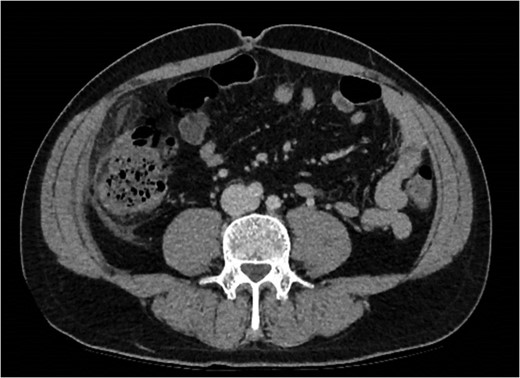

On laparoscopy, a 7–10 cm right-sided segment of greater omentum was inflamed and necrotic, without adjacent mischief or signs of omental torsion (Fig. 3). The caecum and ascending colon were entirely normal (Fig. 4). The appendix was retrocaecal and retroperitoneal. The appendix was not dissected to visualize the entire length; the infarcted omentum was discrete to this. An omental necrosectomy was not performed due to the risks of this bleeding and potential diathermy injury risk. Rather, accepting the risk of protracted symptoms from minor omentum necrosis.